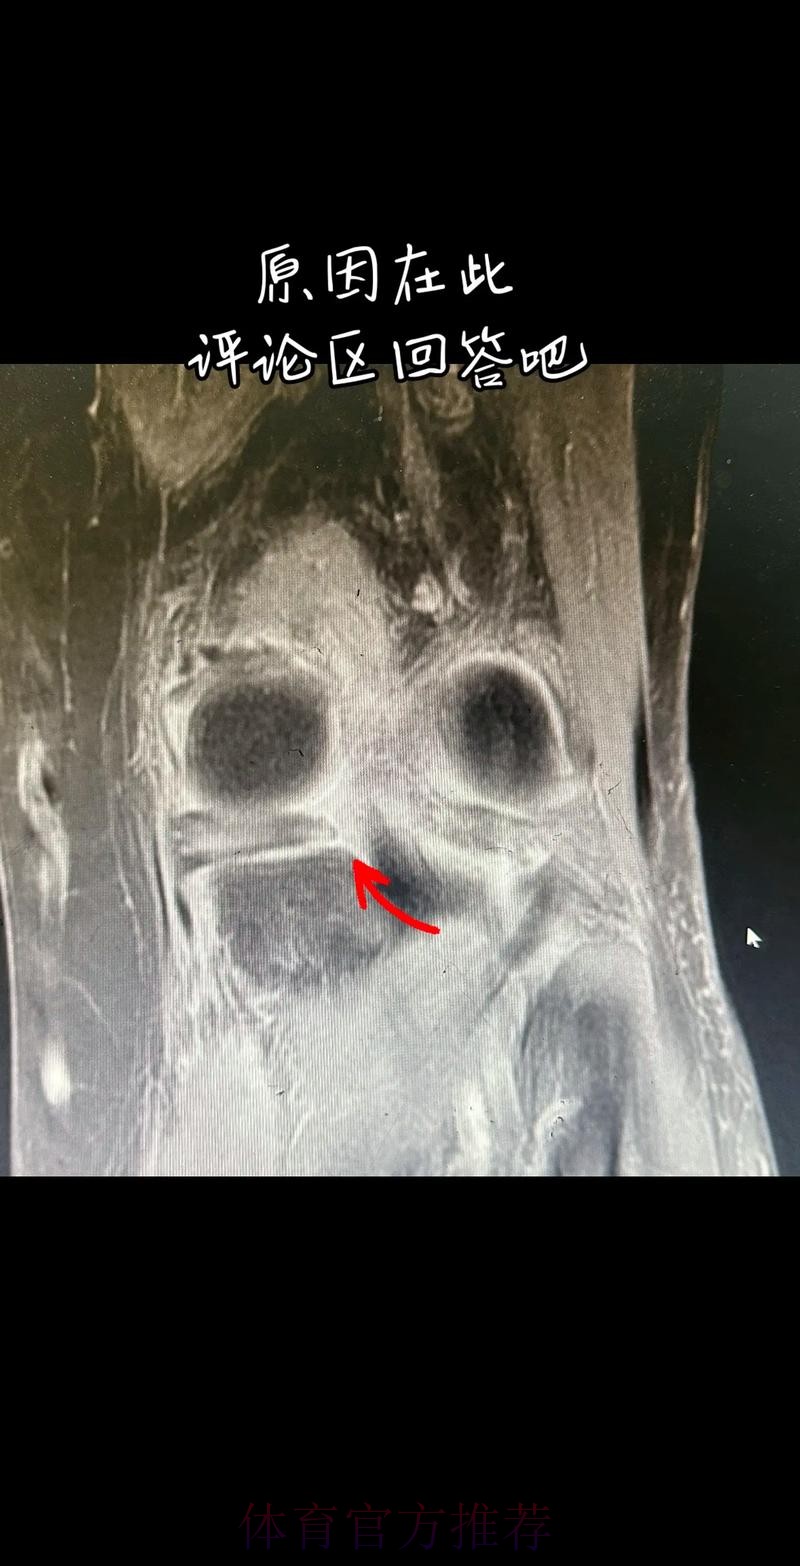

从医学角度看 半月板是膝关节内一块呈“C”形的软骨结构 其作用是缓冲冲击 稳定膝关节 并帮助分散压力 “左膝内侧半月板撕裂”通常说明在一次急停 旋转 或对抗中 半月板受到了超过其承受极限的力导致结构损伤 这类伤病常见于足球 篮球等需要频繁变向和对抗的项目 对于职业球员而言 半月板损伤严重程度不一 但共同点是都会影响支撑发力 跳跃以及变向时的稳定性 而官方给出的“预计伤缺6-8周”这个时间区间 往往对应的是中度损伤或通过微创手术加积极康复能够较快回归的情况 也意味着暂时没有出现必须长时间休战的最坏结果